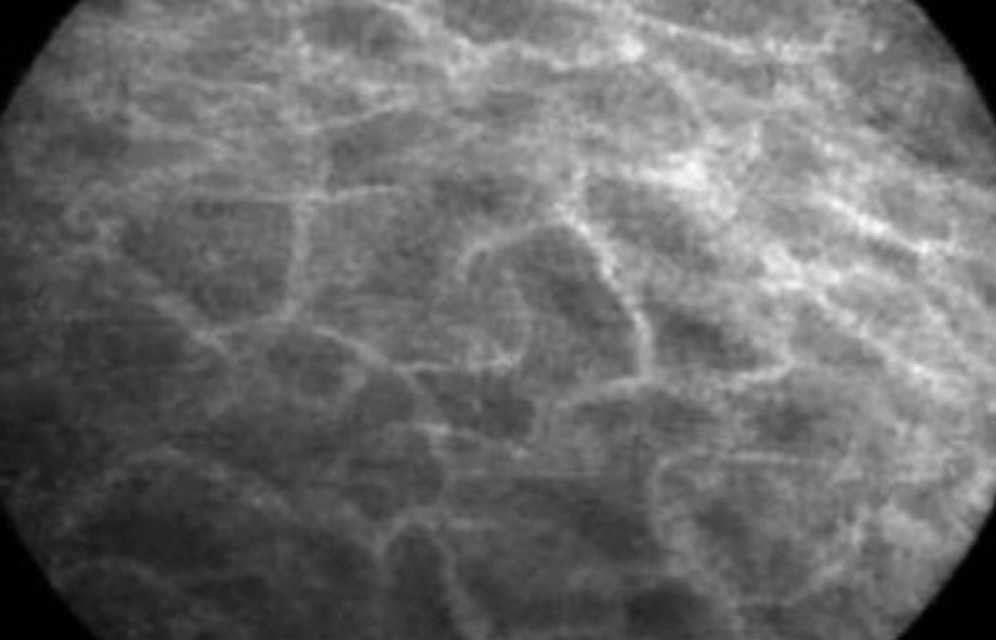

Сеть каналов была обнаружена случайно во время эндоскопии, когда врачи осматривали изнутри желудочно-кишечный тракт пациента. Разглядывая желчный проток, они обнаружили, что окружающие его ткани не плотные и однородные, как считалось ранее, а пронизаны сетью неизвестных каналов. Сначала исследователи решили, что перед ними просто капилляры, но в таком случае сами капилляры, заполненные жидкостью, при микроскопическом исследовании должны быть затемнены, а ткань между ними быть более светлой. Однако перед учеными была совершенно противоположная картина.